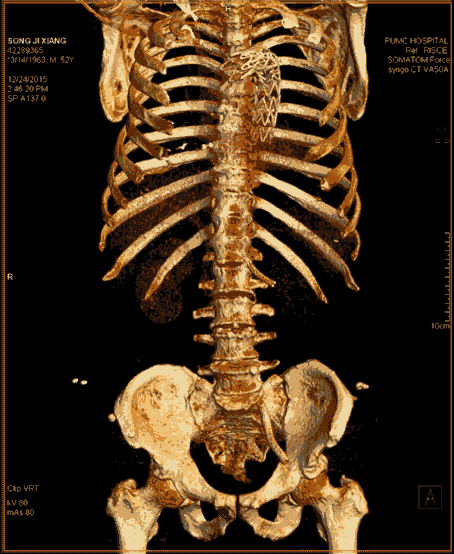

近日,代表當(dāng)前CT最高水平的西門子SOMATOM Force開源CT在滕州市中心人民醫(yī)院正式啟用。Force CT采用全球獨創(chuàng)的雙球管、雙探測器結(jié)構(gòu),臨床應(yīng)用領(lǐng)域廣泛,在全身各部位的無創(chuàng)成像方面開創(chuàng)了高端CT應(yīng)用的新紀(jì)元,尤其在冠心病冠脈成像方面有無可比擬的優(yōu)勢,其操作便捷、安全無創(chuàng)和綠色環(huán)保引領(lǐng)著業(yè)內(nèi)的標(biāo)桿和典范,被稱為“窺心神器”。

Force CT以超低的輻射、精準(zhǔn)的診斷,開創(chuàng)了CT安全篩查的新時代。

SOMATOM Force是全新的第三代雙源CT,革新了球管、高壓發(fā)生器、探測器、數(shù)據(jù)采集系統(tǒng)、重建系統(tǒng)等一系列影像鏈,定義了一個無與倫比的 CT 性能等級,開辟了全新的CT影像時代,可以做到更快、更寬、更能、更低。

Force CT轉(zhuǎn)速可達(dá)0.25s/圈,雙套球管及探測器交叉90度設(shè)計,相當(dāng)于單源CT 0.125秒每圈,心臟成像時間分辨率66ms,真正跨越自由心跳門檻100ms,因此可以做到自由心率的心臟冠脈CTA等檢查。

西門子獨創(chuàng)的Turbo Flash模式,掃描速度達(dá)每秒73.7cm/s,可在1秒內(nèi)完成胸腹大血管、頭頸心一站式篩查,對胸痛三聯(lián)征、心腦聯(lián)合成像、頭胸心腹部及全程主動脈等多部位一站式聯(lián)合掃描等檢查都能很好的完成。